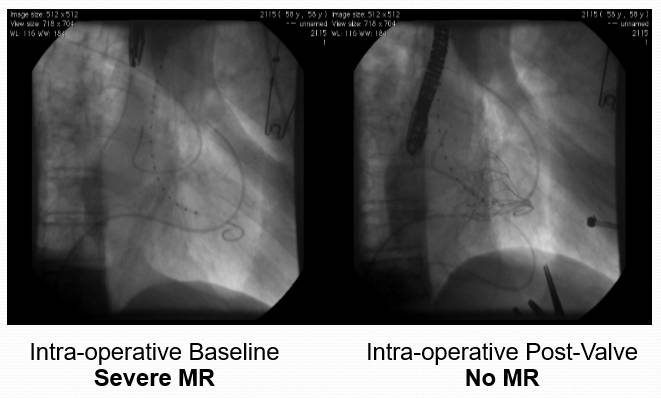

经导管二尖瓣修复术-MitraClip

技术原理:使用特制的二尖瓣夹合器,经股静脉进入,穿刺房间隔,进入左心房及左室,在三维超声及DSA引导下,使用二尖瓣夹合器夹住二尖瓣前、后叶的中部,使二尖瓣在收缩期由大的单孔变成小的双孔,从而减少二尖瓣反流

MitraClip技术过程

超声评价

超声提示严重MR

释放Clip后反流明显减轻

三维超声下显示二尖瓣呈双孔